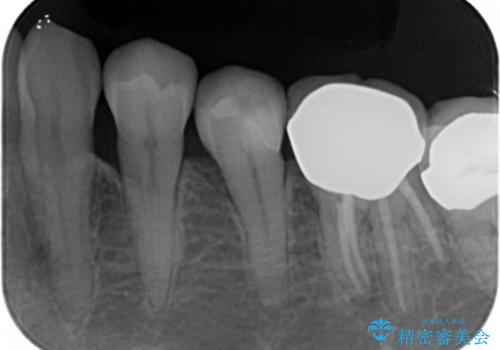

古い詰め物とう蝕を除去し、審美的で適合が良く二次う蝕になりにくいセラミックインレーによる修復を行いました。

審美的な仕上がりと自然な咬み心地に喜んで下さいました。

インレーの種類:セラミックインレー(e-max press)